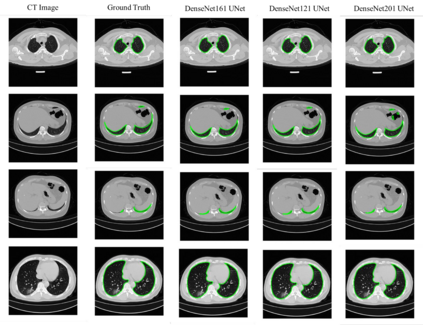

Since the breakout of coronavirus disease (COVID-19), the computer-aided diagnosis has become a necessity to prevent the spread of the virus. Detecting COVID-19 at an early stage is essential to reduce the mortality risk of the patients. In this study, a cascaded system is proposed to segment the lung, detect, localize, and quantify COVID-19 infections from computed tomography (CT) images Furthermore, the system classifies the severity of COVID-19 as mild, moderate, severe, or critical based on the percentage of infected lungs. An extensive set of experiments were performed using state-of-the-art deep Encoder-Decoder Convolutional Neural Networks (ED-CNNs), UNet, and Feature Pyramid Network (FPN), with different backbone (encoder) structures using the variants of DenseNet and ResNet. The conducted experiments showed the best performance for lung region segmentation with Dice Similarity Coefficient (DSC) of 97.19% and Intersection over Union (IoU) of 95.10% using U-Net model with the DenseNet 161 encoder. Furthermore, the proposed system achieved an elegant performance for COVID-19 infection segmentation with a DSC of 94.13% and IoU of 91.85% using the FPN model with the DenseNet201 encoder. The achieved performance is significantly superior to previous methods for COVID-19 lesion localization. Besides, the proposed system can reliably localize infection of various shapes and sizes, especially small infection regions, which are rarely considered in recent studies. Moreover, the proposed system achieved high COVID-19 detection performance with 99.64% sensitivity and 98.72% specificity. Finally, the system was able to discriminate between different severity levels of COVID-19 infection over a dataset of 1,110 subjects with sensitivity values of 98.3%, 71.2%, 77.8%, and 100% for mild, moderate, severe, and critical infections, respectively.